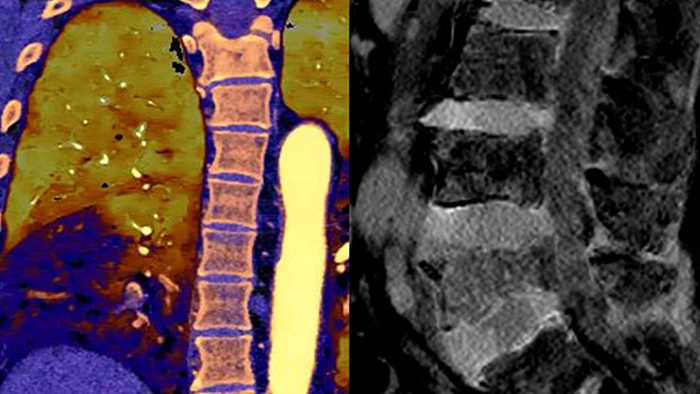

Spectral CT 7500 provides advanced diagnostic capabilities through a single spectral scan, enabling accurate diagnoses and expediting treatment times. Expand patient care with a one-stop solution across radiology, cardiology, oncology, neurology and trauma. Easy workflow with high image quality, low dose and spectral results. Scan in seconds as you normally would for conventional CT with immediate access to spectral CT results that can help eliminate the need for multiple CT scans or even additional scans from other modalities.

With Spectral CT 7500, a single spectral scan offers advanced diagnostic capabilities to help speed time to treatment. Expand patient care with a one-stop solution across radiology, cardiology, oncology, neurology and ED/trauma.

Detector-based spectral allows the coronaries and myocardium to be assessed in a single exam. Spectral CCTA results can mean that patients avoid an invasive and expensive procedure in the cath lab. Perform comprehensive cardiac evaluations quickly, including perfusion and delayed enhancement studies, all without increased radiation dose

Detector-based spectral results can save the costs of repeat scans and contrast media, and potentially avoid scans from other modalities.